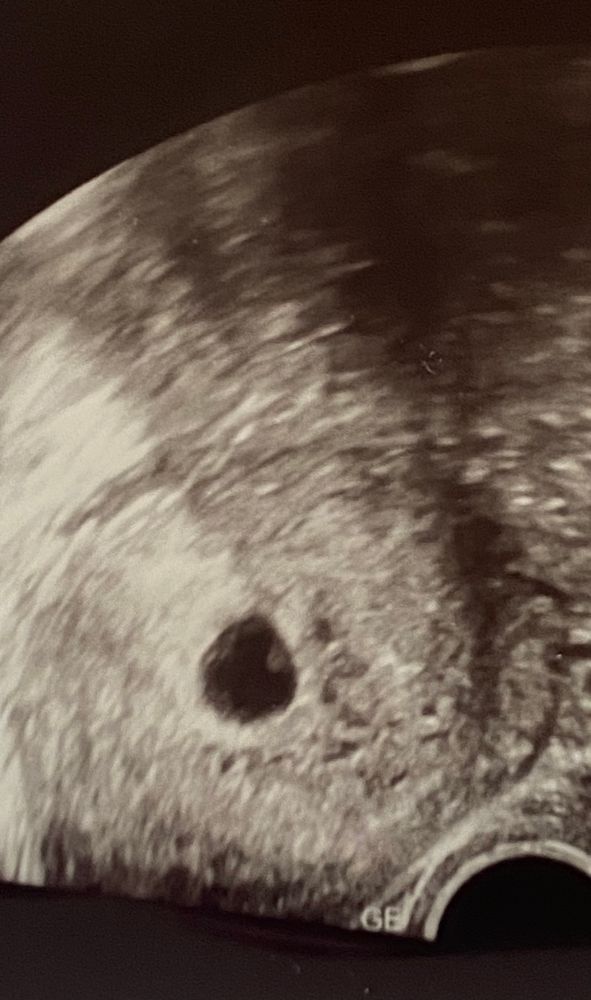

Как я поняла, в 30-45% все таки совпадает, а у вас как? Мне тут кажется девочка, а вам? Узи вагинальное, примерно 5-6 недель.

У вас фото перевёрнуто,хорион вроде слева,слева на мальчика,но у меня не совпало,у меня все слева были и все по передней стенке,и 2 мальчика и девочка,так что 50/50